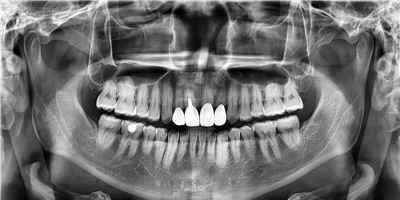

치아 변색 외부 요인

치아 변색 내부 원인